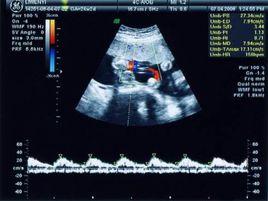

系統彩超就是套用高解析度的彩色都卜勒血流顯像儀對胎兒全身做系統的檢查。所有高解析度的彩超儀器都可以做此項檢查,檢查的內容包含胎兒的脊椎、頭顱、顏面部、心臟、腹部(胃、肝、腎、膀胱)、肢體等。

系統彩超的主要作用是為了排查畸胎,確保胎兒在母體腹中健康發育與生長,系統彩超是孕婦產檢重要項目之一,它能提供包括胎兒頭部、四肢、各個臟器進行逐一篩查,排查畸胎提供準確的科學依據。

最佳時間孕媽媽如果準備做系統彩超檢查,那么在懷孕24-27周是比較好的,因為這個時期胎兒的各個器官組織發育已趨完善,胎兒大小及羊水適中,受骨骼回聲影響較小,超聲診斷圖像清晰,所以這個時候做相應的超聲檢查是非常科學的,孕媽媽一定不要錯過適宜檢查時間!